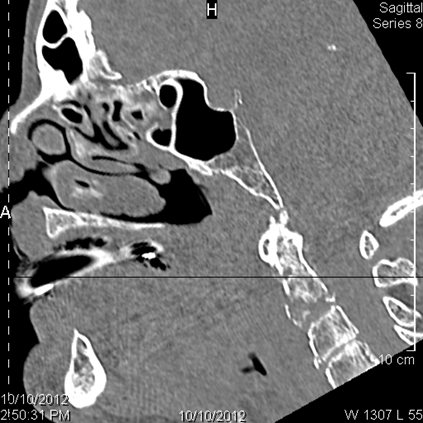

Central Skull Base

There is a fracture of the greater or lesser wing of the sphenoid bone or basisphenoid.

Cervical Spine

The visualized portions of the cervical spine are abnormal for the patient’s age.